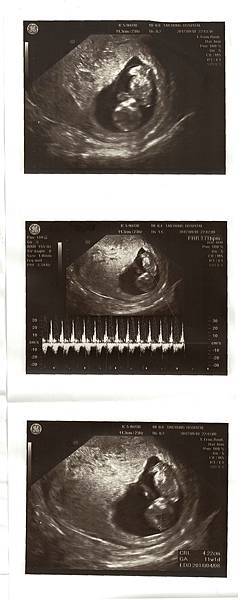

8W3D 9/4回診照心跳,兩週的等待很漫長,到了要照心跳的那天,我和Chris不由自主緊張了起來,也許是上次的經驗讓我們格外緊張與焦慮。一進診間,劉醫師說今天要照心跳喔!

照超音波的時候,醫師一直在肚子上來回滑著儀器,我看著畫面,胚囊明顯變大,但是裡面的東西卻看不清楚,我和Chris開始緊張了起來,躺在診台上的我心臟跳得超快,真的好緊張。

醫師突然請我去廁所把小便解掉,要照陰超看看,還說:照理來說八周應該要有心跳了。聽到這句話的我和Chris整個快無力了~Chris說他當時內心吶喊:不會吧!!

上完廁所後又躺上診台準備照陰道超音波,結果照得好清楚,變大的胚囊裡面已經有胚胎了,劉醫師看著畫面跟我們細心解釋,圓圓的卵黃,是寶寶自己帶的便當,很好喔!

目前大小也在標準值,一邊聽我還是一邊緊張,因為最重要的是我們期待著的心跳聲。接著劉醫師說:來,我們聽聽心跳聲。

“碰碰碰碰碰碰”!好快好有力的聲音,醫師說一分鐘167下,160-180下都是正常的哦!

聽到寶寶心跳聲的當下覺得自己在發抖,也覺得好神奇,肚子裡有了第二個心跳聲。

(看著超音波照片就開始覺得寶寶可愛了)

晚上做第一次產檢,候診的人好多,等到十點多才看診,因為子宮後傾,腹超還是照不清楚,這次一樣照了陰超。

寶寶長大了~!

其實因為上次的經驗,讓我跟Chris每次的檢查都蠻緊張的,結果這次聽到醫生指著照片說:這是他的頭、手、腳⋯的時候,我看見Chris終於露出了笑容(覺得自己小孩很可愛的那種笑容)

看到他這麼開心,真的好幸福。寶寶這次的心跳聲是171,醫生說很正常哦,大小4.22cm也很好~後來我們看照片,原本的10W4D變成了11W1D,預產期日期也提前了~